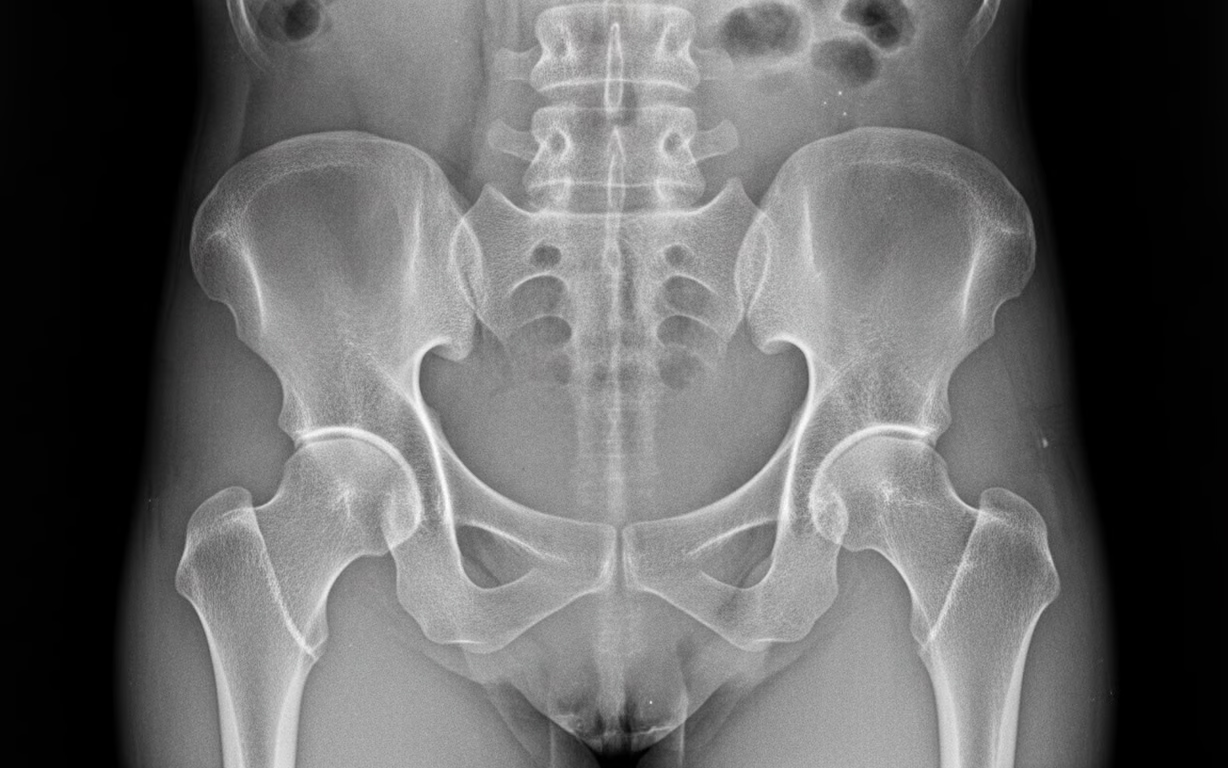

- Radiografii osoase, care pot evidenția:

- demineralizare osoasă difuză;

- subțierea cortexului osos;

- fracturi sau zone Looser (fracturi incomplete), caracteristice osteomalaciei.